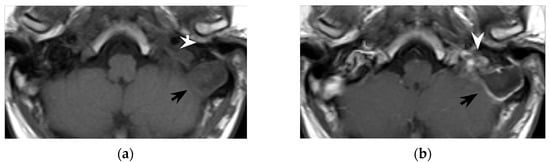

Figure 1. Normal anatomy, post-contrast axial CT (a,b). In the same images with annotations (c,d), the digastric muscle (white arrowhead) and the sternocleidomastoid muscle (white arrow) delimitate the posterior cervical space (red). The carotid artery can be identified nearby (black arrow).